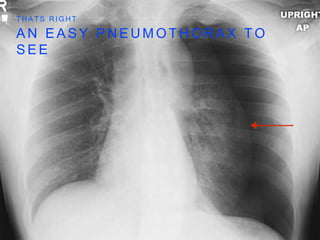

W H AT S T H E D X ? P T W I T H A S T A B T O L E F T C H E S T W A L L

A N EA S Y P N E U M O T H O R A X T O S E E T H A T S R I G H T